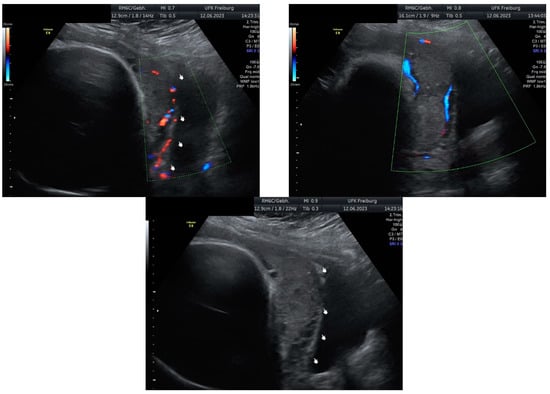

Sonographic findings (Figure 12):

Figure 12.

Enlarged vascular spaces within the placenta; A focal mass invading the myometrium, suggestive of placenta accreta; Hypervascularity noted at the interface between the serosa (outer uterine layer) and bladder.

These findings are characteristic of placenta accreta, a condition where the placenta attaches too deeply into the uterine wall, potentially leading to complications such as excessive bleeding during delivery. The hypervascularity at the serosa–bladder interface indicates the abnormal and increased blood flow associated with this condition. These imaging findings are crucial for diagnosis and guiding management decisions in cases of placenta accreta.